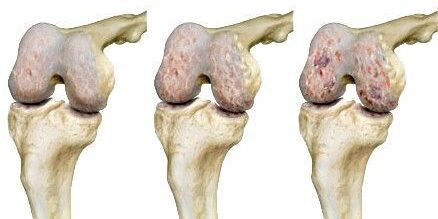

Elsődleges porckopás, arthrosis esetén külön kiváltó ok nélkül, lassan, észrevétlenül fogy el az ízületi porc a beteg ízületből. Az elsődleges porckopás és arthrosis igazi oka ismeretlen, az eddigi kutatási eredmények alapján feltételezhető, hogy öröklött genetikai tényezők, bizonyos anyagcsere-rendellenességek, illetve az ízületi folyadék összetételének hátrányos megváltozása áll a jelenség hátterében. Ezért a porckopás, arthrosis elsődleges formáját természetes folyamatnak tartjuk, mely az öregedési folyamat része.

Másodlagos porckopás, arthrosis esetén azonban az ízület korábbi sérülése indítja el a porckopás folyamatát (pl. porckorong szakadás, keresztszalag szakadás, oldalszalag problémák, ízületbe hatoló csonttörés). Ez a forma általában már fiatalabb korban jelentkezik, mint az idősebbeket érintő elsődleges porckopás, arthrosis.

A porckopás, arthrosis korai stádiumában a porcsejtek igyekeznek a sérült sejt közötti állományt kijavítani, ahogy azonban a porckopás folyamata halad előre, a porcsejtek kifáradnak, és már nem tudják pótolni az elveszett molekulákat. A tünetek ilyenkor már nagyon fájdalmasak lehetnek.

A porckopás, arthrosis diagnózisának legfontosabb eszköze ma is a röntgenvizsgálat. Porckopás estén a felvételeken jól látható az ízületi rés beszűkülése, a csont ízület alatti elváltozásai: megvastagodása, ciszta. A röntgenkép és a tünetek gyakorta nincsenek összhangban. Olykor a súlyosnak látszó arthrosis, porckopás meglepően tünetszegény, máskor minimális röntgenelváltozások mellett is drámaiak a tünetek.